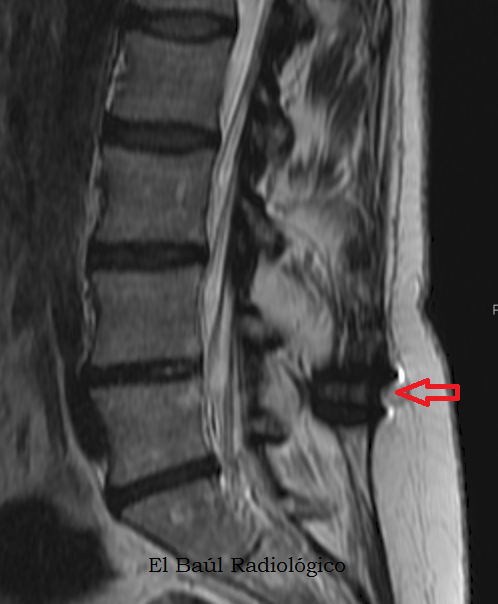

FIGURA 6)  En las exploraciones de TRM de columna los implantes se distinguen con mayor dificultad, como una zona oscura intervertebral. Más llamativas  son las bandas brillantes que se producen en el tejido esponjoso de las vértebras adyacentes,  por microfracturas trabeculares (flechas rojas).

(On MRI scans of the spine, the implants are distinguished with difficulty, as an intervertebral dark area. More striking is the finding of bright bands in the cancellous tissue of adjacent vertebrae, produced for trabecular microfractures (red arrows).